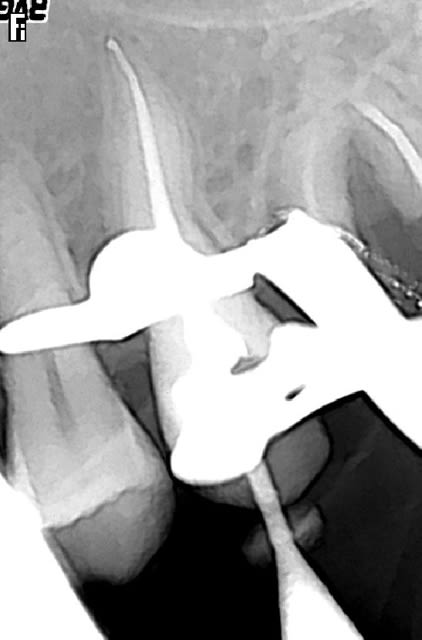

- fausse route bouchée au MTA

-instrument fracturé impossible à retirer, je suis passée à côté et je l'ai noyé dans la gutta chaude.

Reprise avant instrument fractur  lwjzpw - Eugenol

Lime 15 noy e dans gutta qvvcdp - Eugenol